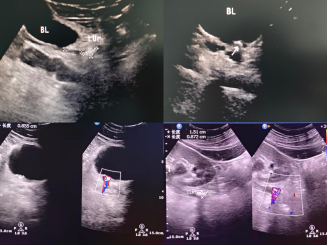

影像学检查:B超和下腹X线片容易确诊,复杂的病例可以采用CT平扫检查帮助诊断,必要时行膀胱镜检查,可以通过这些检查来确定结石的大小、位置以及是否需要手术等。